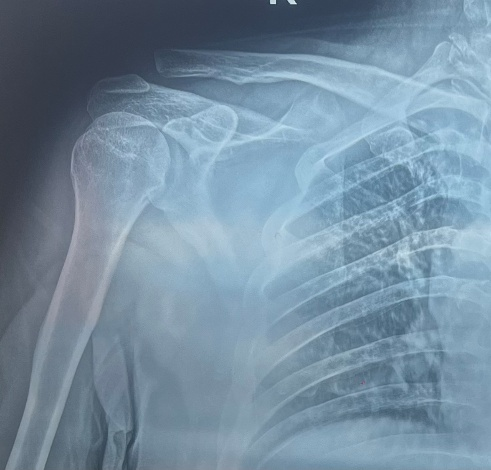

患者黄某,因骑车摔倒致右肩锁关节脱位,术前畸形明显、疼痛剧烈。术后次日即开始被动活动,疼痛显著下降,第3天出院,肩部外形恢复正常,对微创效果非常满意。

术前